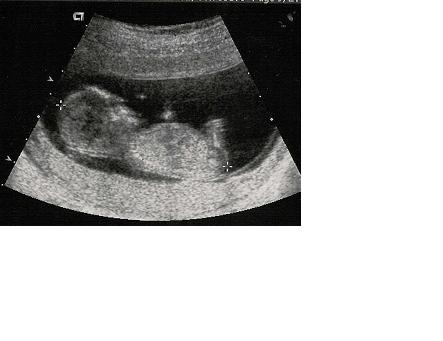

Suzanne discovers that she is pregnant (and not just fat as Scott had suggested). She calls Dr. Zachary, famed gynecologist and spelunker for help.

This is what he saw....